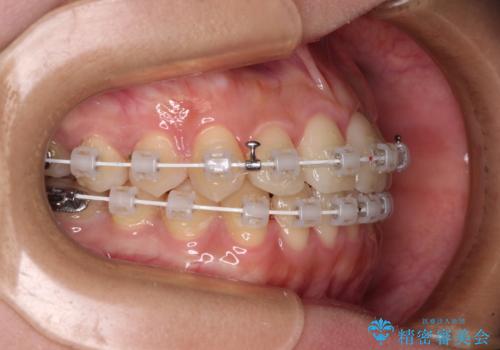

前歯のクロスバイトを短期間で解消 目立たないワイヤー矯正

- 審美装置

- 1年1ヶ月

- 前歯のクロスバイトを治したいとのことで来院された患者様です。

できる限り楽して、短期間で治したいとのことで、ワイヤー装置にて矯正治療を行うこととしました。